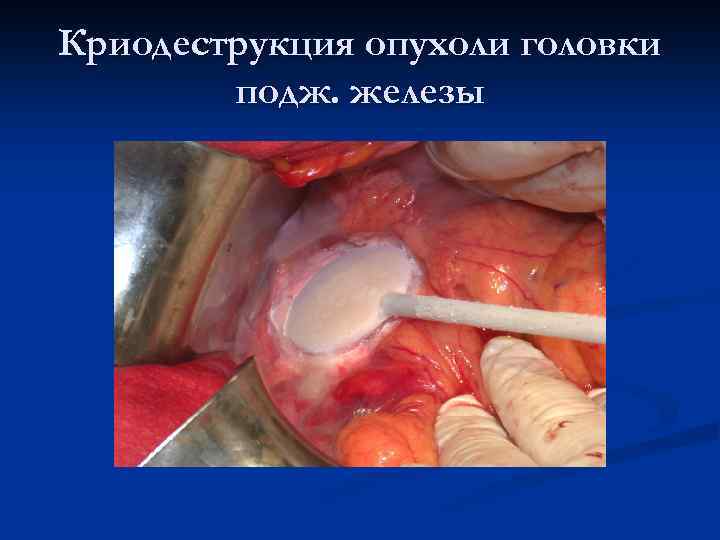

Криодеструкция опухоли головки подж. железы

Криодеструкция опухоли головки подж. железы